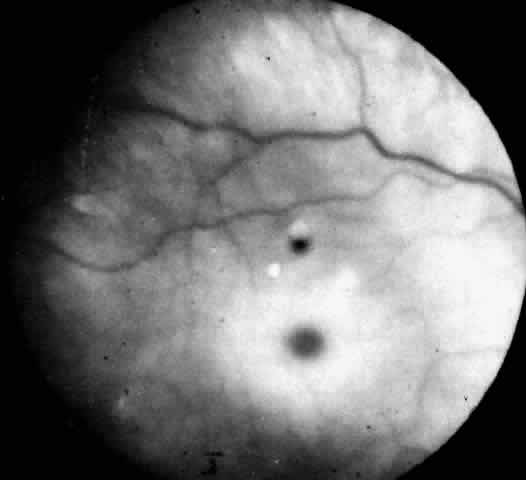

Recognition of the cherry-red spot at the macula is a major diagnostic criterion of Tay-Sachs disease (Fig. 3). It is caused by the accumulation of intracytoplasmic membranous bodies in retinal ganglion cells.

|

The circular appearance of the fundoscopic lesion reflects the anatomy of the macula. No ganglion cells are present at the very center of the macular region, the foveola, and the central red spot simply represents the normal choroidal background color. The ganglion cell layer surrounding the foveola is several cells thick, and loading of these neurons by storage products results in loss of retinal transparency and a white parafoveal halo. Peripheral to the macular region the ganglion cell layer is only one cell thick, and lipid accumulation in these cells is, therefore, less conspicuous.

Tay-Sachs disease is also the most common storage disease causing macular cherry-red spots (Table 2).3 The variation in the shade of the red spot reflects racial fundus pigmentation. The halo is opaque, slightly elevated, and 1.5 disc diameters in width. The outer border is less sharp than the inner border.

A dynamic process of development of the macular cherry-red spot occurs paralleling the infant's progressive neurologic disorder. The cherry-red spot can be observed as early as 2 months of age and is conspicuous at age 4 to 6 months. Loss of visual acuity may occur without noticeable change in the circular halo. But, in time, the ganglion cells atrophy and optic atrophy and loss of the nerve fiber layer occurs. At this stage blindness coincides.